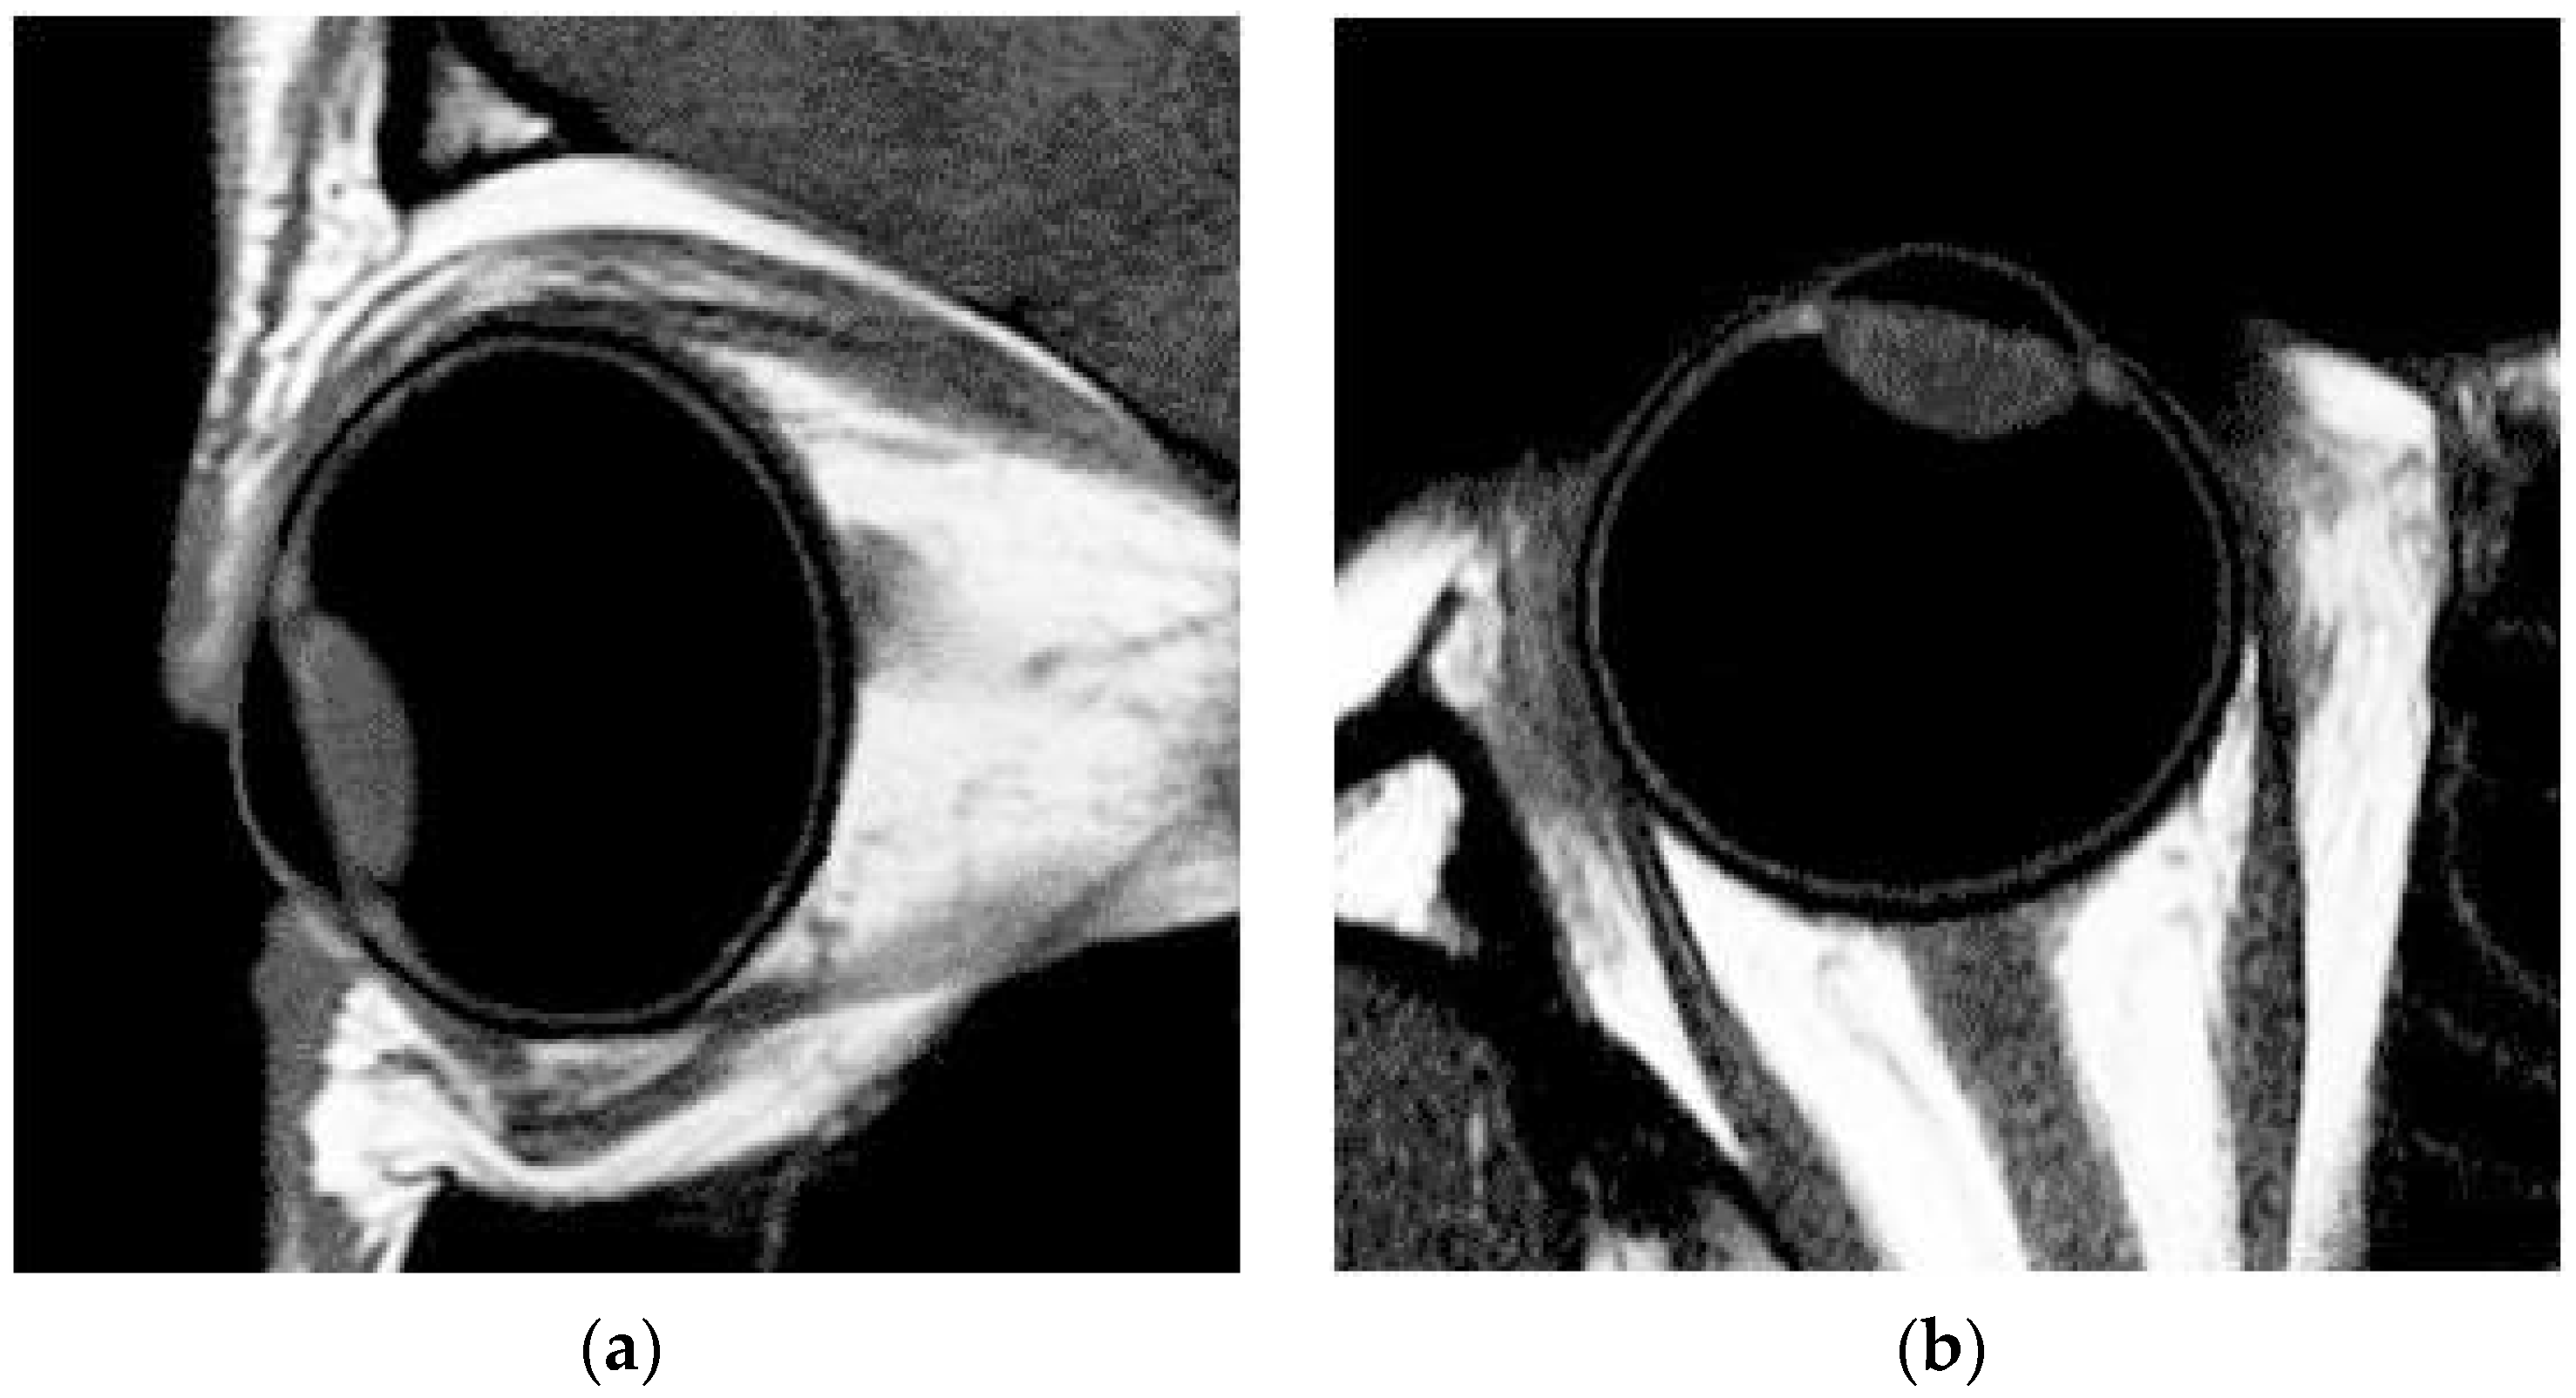

The data of MRI were analyzed with custom-written software MATLAB (MATLAB 8.0 program). The 2-D curvature of the retina for both the tangential and sagittal sections was determined for the corresponding horizontal and vertical meridians measured in peripheral refraction. The MRI pictures of one of the subjects are shown in Figure 1a,b to help explain how the retinal curvature was determined. The axial length measured with MRIs was compared with A-scan ultrasound measurement (Axis-II A-scan, Quantel Medical, Rockwall, TX, USA) during a distant fixation in the same eye for each participant to confirm the dimension of the eyeball as both the measurements were similar. Various biometric parameters were measured and determined automatically based on the collected MRI images by MATLAB [25] and Rhinoceros [26].

The sequence of data analysis was as follows: (1) an MR image was converted into grayscale using MATLAB software (see Figure 1a,b); (2) according to the distribution of pixel levels, the threshold of the image matrix was tuned to determine the boundaries of cornea, lens, and retina (see Figure 1c; for example, the grayscale values which represent the regions of the retina and the vitreous were above 0.35 and below 0.2, respectively, in the same MRI pictures. Therefore, the threshold value was set to be 0.275 for clearly identifying the shape of retina, and (3) the coordinates of the boundaries and their corresponding dimensions were illustrated using Rhinoceros (see Figure 1d). In this case, since the retinal profile consisted of a thickness of a few pixels, the possible radius value R was distributed within a range, rather than a single value, such as the values 10.64, 11.01, and 11.88 mm shown in Figure 1d, which were applied for data analysis of retinal shape simulation (see Section 2.4).

Figure 1. (a) Tangential axial MR image of one of the subjects. (b) Sagittal axial MR image of one of the subjects. (c) Various biometric parameters were measured using magnetic resonance imaging. (d) The curvature of the retina was calculated using the Rhinoceros.